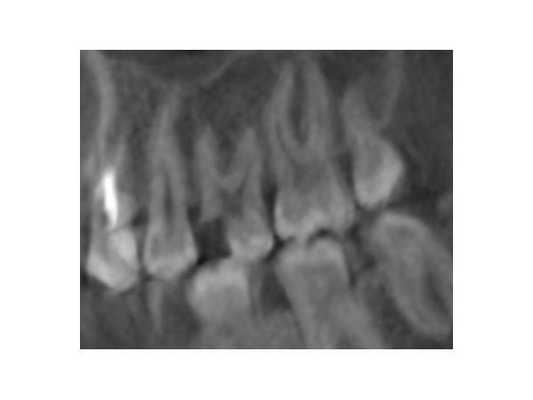

Лечение витальной ампутацией, позволившей сохранить жизнеспособность корневой пульпы, ее активное функционирование, проведено 39 пациентам в возрасте от 16 до 56 лет. Среди пациентов было 15 мужчин и 24 женщин. По данным клинического обследования у 2 больных был острый частичный, у 11 - острый общий (в том числе в 5 случаях отмечалась незначительно выраженная перкуторная реакция), у 23 - хронический простой, у 3 - обострение хронического пульпита. Проведенное до лечения рентгенологическое исследование показало, что в 34 зубах не было каких-либо изменений со стороны периапикальных тканей, а в 5 случаях наблюдалось расширение периодонтальной щели.

Клиническое наблюдение за больными осуществляли непосредственно после лечения, а также спустя 2 года. До лечения и в отдаленные сроки пациентам проводилась рентгенография.

Через 2 года после лечения было обследовано 33 пациента. 32 из них жалоб не предъявляли. При клиническом осмотре слизистая оболочка десны в проекции верхушек корней была без видимых патологических изменений, пломбы сохранены, перкуссия безболезненная. У одного пациента периодически возникали боли от горячего в излеченном зубе, а вертикальная перкуссия была слабо болезненной. Зуб перелечен витальной экстирпацией. При рентгенологическом обследовании 5 пациентов с первоначальными незначительными изменениями в периодонте у 2 пациентов выявлены эти изменения. Они остались не увеличенными. В 3 случаях изменения в периапикальных тканях имели тенденцию к замещению склерозированной костной тканью. Таким образом, во всех 33 случаях наблюдалось клиническое благополучие, в 31 случае - рентгенологическое. Положительные результаты лечения через два года получены в 94% случаев.